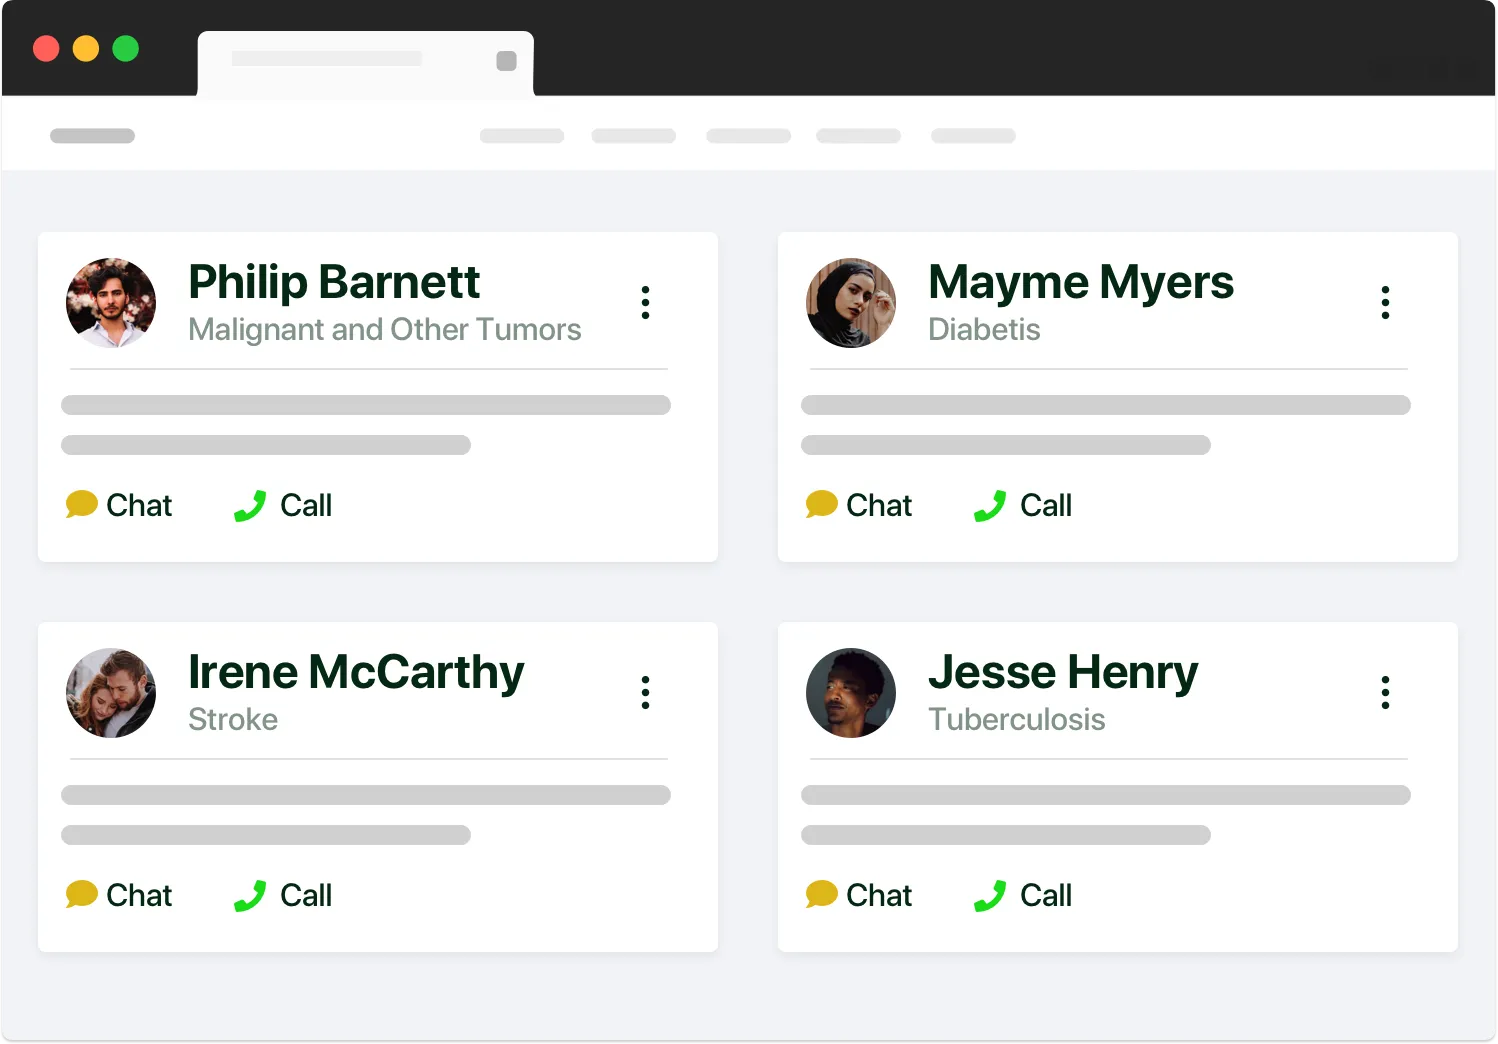

Secure Messaging: Encrypted messaging between patients and providers.

Real-time Chat Support: Offer live patient/provider support through chat.

Feedback & Ratings: Continuous improvement through patient feedback.